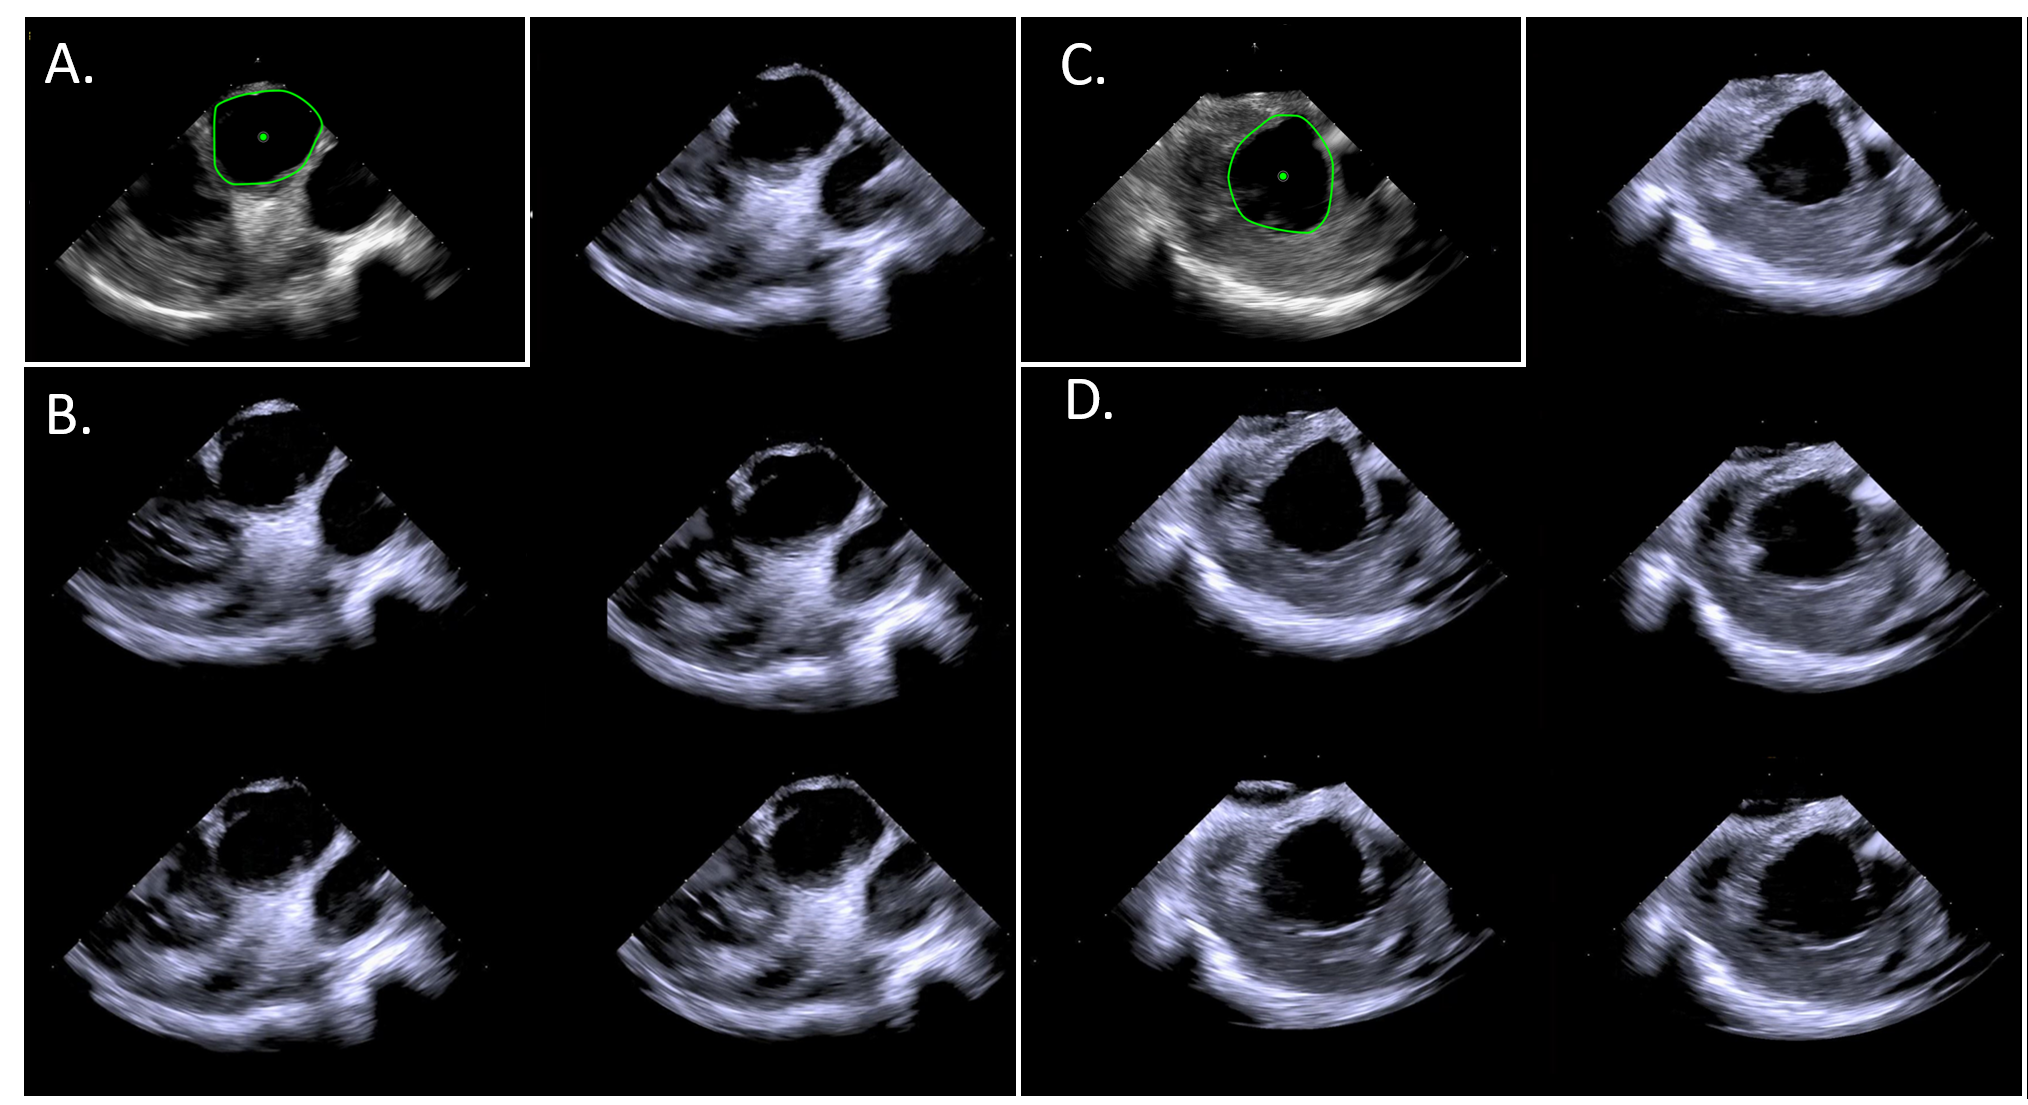

Refer to caption

Figure 8: Example results from in vivo validation experiments. (A) the initial view of the Tricuspid Valve from joystick control by the interventionalist. (B-D) reacquisitions by semi-autonomous robotic control of the ICE catheter. (E) presents the ground-truth catheter position of (A) in green and (B-D) in magenta, cyan, and yellow respectively. Manually labeled in-image ROI are also shown in (A).

Figure 9: (A,C) Reference and (B,D) automatically reacquired images of the Aortic and Mitral valves respectively. Manually labeled in-image ROI are shown in (A,C).

Initial ultrasound views of the Aortic, Mitral, and Tricuspid valve imaging targets were manipulated to and saved by the physician using joystick input to the robotic controller. Views were then automatically returned to in series several times by automated robotic control (e.g. consecutively cycling through return to Aortic valve, return to Mitral valve, return to Tricuspid valve). The ultrasound image was recorded for several heart cycles and a DCT image was acquired for each viewing of an anatomical target. These data were then compared to measure the reproducibility of robot controlled catheter tip motions. In total, three independent animal experiments evaluating automated view recovery were performed with four, six, and seven imaging events respectively per image target, resulting in 51 total view recoveries.

In animal catheter tip localization error from DCT is presented in Table II for each imaging target. Across all image-targets, average catheter tip localization error was 1.5±0.9plus-or-minus1.50.91.5\pm 0.9 mm.

IV-B4 Animal validation of automated view recovery, image analysis

Example images from independent robotic re-acquisitions of the Tricuspid valve are presented in Figure 8 alongside the corresponding ground-truth catheter segmentations from DCT. Further examples of the Aortic and Mitral valves are presented in Figure 9. Image similarity as measured by image cross-correlation is presented in Table II for each image target. Average image similarity across all image-targets and experiments was 81.1±6.9%plus-or-minus81.1percent6.981.1\pm 6.9~{}\%. For comparison and to establish a relative maximum achievable similarity, the average image similarity when comparing images from immediately consecutive heart cycles (i.e. without moving the catheter) was 89.8%percent89.889.8~{}\%. This value represents the an aggregate of the observable noise resulting from slight variations in cardiac rhythm, respiratory motion, and ultrasound speckle.

Finally, in-image ROI were designated for each image target based on visible anatomy (Figures 8(A) and 9(A,C)). ROI centroids were then measured relative to corresponding reference ROI to quantify the localization of ROI relative to the imager. Average in-image ROI localization error across all image-targets was 2.9±2.2plus-or-minus2.92.22.9\pm 2.2. Again for comparison and to establish an accuracy floor, average ROI localization error when comparing ROI from immediately consecutive heart cycles (i.e. without moving the catheter) was 2.02.02.0 mm.